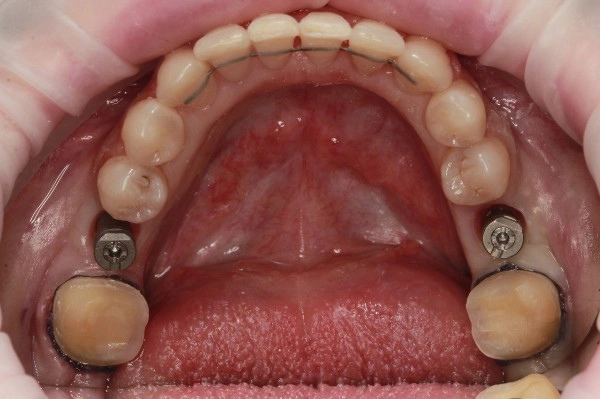

Установлены 2 коронки на импланты с индивидуальным циркониевым абатментом. На задние сильно разрушенные жевательные зубы установлены керамические накладки.

Работа врача - ортодонта Глуховой Татьяны Александровны и врача - ортопеда Никитина Никиты Юрьевича.